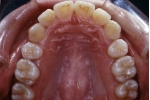

| 治療前後の比較

カテゴリー:Class Ⅱ division 1(抜歯症例)

大臼歯関係がclassⅡ、overjet 6mm以上、U1-SN 110度以上、ANB 6度以上が望ましいという条件は第二症例と同じ。FMAの条件がはずれた代わりに、抜歯ケースとして治療することを必須とする。